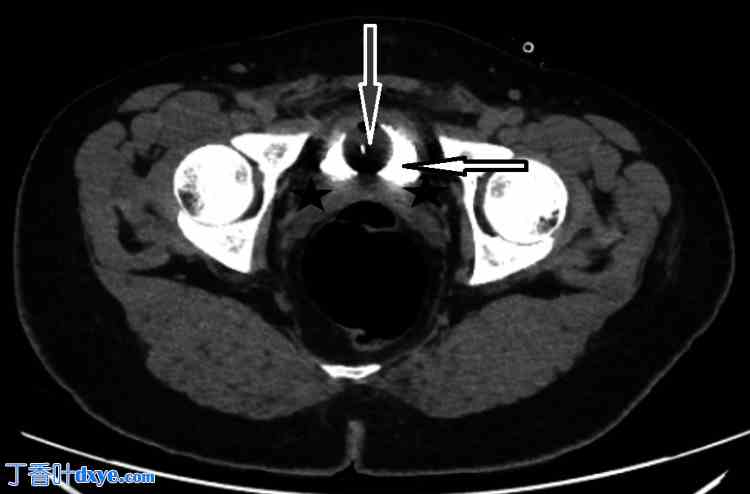

术后,患者恢复良好,仅下腹部不适。术后第1天(POD 1),血液检查结果显示白细胞计数(WCC)为13.11 x 10³/μL(参考值2.2-10),C反应蛋白(CRP)为69.23 mg/L(参考值0-5)。引流液仅为15 ml,呈浆液血性。然而,术后第2天(POD 2),引流量增至55 ml,术后第3天(POD 3)增至220 ml。此时,怀疑存在漏诊的膀胱损伤,引流液分析证实了这一诊断,引流液肌酐水平为11354 μmol/L(参考值3450-22900),而患者血清肌酐水平为69 μmol/L(参考值45-100)。插入Foley™导尿管(Microtech,德国门兴格拉德巴赫),并安排进行腹盆部CT扫描。CT延迟期显示输尿管或膀胱无明显造影剂渗漏,盆腔内仅有少量游离液体(如图1-2所示)。CT结果支持轻微膀胱损伤已自行愈合的诊断,因为插入Foley导尿管后未见渗漏,这支持了作者对该患者采取保守治疗方案。

图 2. 术后第 3 天腹部 CT 轴位图像(延迟 20 分钟序列),显示膀胱内有造影剂(白色箭头)和导尿管(灰色箭头),膀胱周围区域无造影剂渗漏(黑色星号)。

白色箭头:膀胱内有造影剂,灰色箭头:导尿管,黑色星号:膀胱周围区域无造影剂渗漏